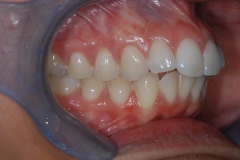

This mouth had recession on just one tooth with very little bone to support the tooth. The area needed support and thickness. The tissue was placed and the area now has thicker tissue to withstand the forces that the patient needs to place on it.

Click on a thumbnail to view the before and after photos.